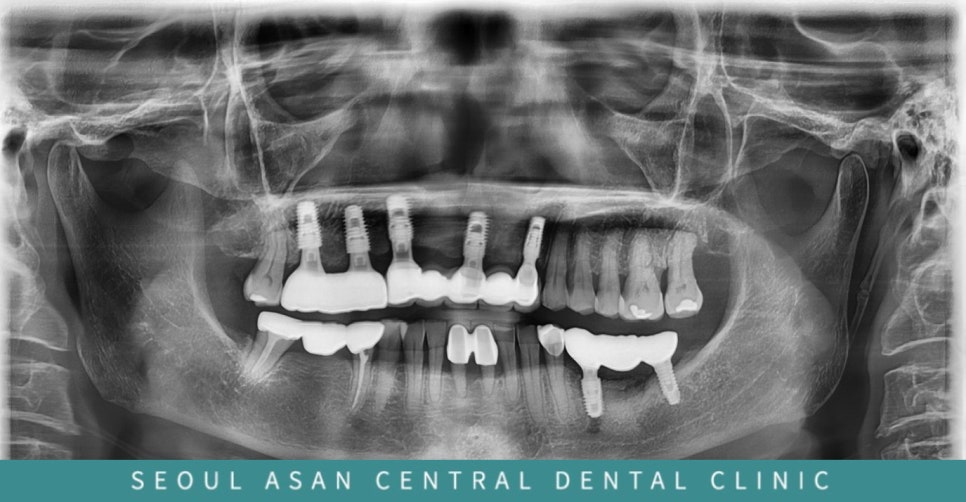

이후에 위 아래 모두 보철물(치아 모양)이 들어간 모습입니다.

아래쪽 뼈이식한 부분도 상태가 많이 좋아졌으며

위에 매복 송곳니가 있던 부위에도 임플란트는 물론

뼈이식 부위가 안전하게 이식된 것을 확인할 수 있었습니다.

이렇게 여러 개의 임플란트를 묶어서 치료하게 될 경우,

장기적인 유지를 위해 정확한 보철물의 안착 및 안정적인 교합이 중요합니다.

이를 전문적으로 공부하는 과가 바로 치.과보철과입니다.